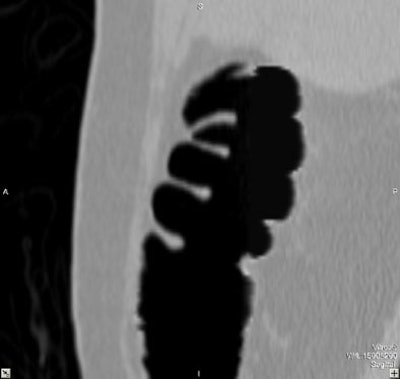

| Virtual colonoscopy images of an asymptomatic 56-year old woman who ingested small aliquots of nonionic iodinated contrast, without dietary restrictions, prior to virtual colonoscopy. The evening before the exam, the patient ingested a half dose of mild cathartic, markedly reduced from standard regimens. Images top to bottom: Sagittal view of cleansed colon following the preparation; corresponding cutaway view; volume-rendered endoluminal views of the same region demonstrate opacificed material in the colon. Further below, the same set of images after the subtraction software has removed opacifying material and reconstructed a natural appearing colonic mucosa, as seen in sagittal; cut-away; and endoluminal (fly-through) views. The green arrow points to some of the contrast which is layering in the dependent portion of the colon. All images courtesy of Dr. Michael Zalis. |